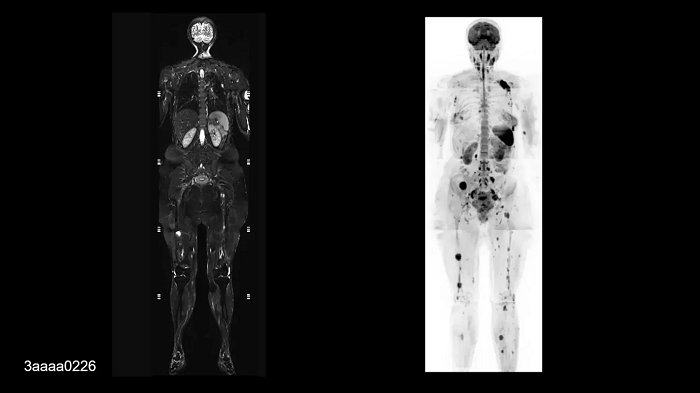

Whole-body imaging

Full Whole-Body Coverage in Only 5 Stations

Enhanced whole-body DWI quality due to BioMatrix SliceAdjust.

- BioMatrix Head/Neck 20

- BioMatrix Spine 72

- 2× Body 18

- Peripheral Angio 36

Image Credit: University Hospital Tubingen, Germany